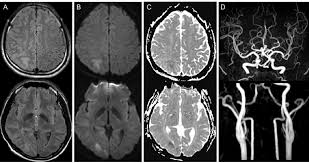

"MRA(Magnetic Resonance Angiography, 자기공명 혈관촬영)"는 MRI를 기반으로 혈관 구조를 영상화한 검사입니다.

- 원리: MRI 기술을 활용하여 혈류 신호를 강조하고, 혈관과 주변 조직을 분리하여 영상화

- 주요 특징: 동맥, 정맥, 혈관 협착, 동맥류 등 혈관 상태 평가에 특화

- 조영제 사용 여부: 일부 경우 가돌리늄 기반 조영제를 사용해 혈류를 더 명확하게 관찰

MRA는 심혈관 질환, 뇌혈관 질환, 말초 혈관 질환 등 혈관 이상 진단에 특히 유용합니다.

(2) MRA 적응증

- 뇌혈관 질환: 동맥류, 뇌경색 위험 평가

- 심혈관 질환: 관상동맥 이상, 대동맥 박리

- 말초혈관 질환: 폐쇄성 혈관질환, 동맥 협착